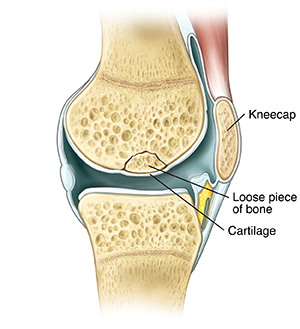

When Your Child Has Osteochondritis Dissecans

Your child has been diagnosed with osteochondritis dissecans (OCD). This is when a small piece of bone and cartilage in a part of a joint separates from the bone around it. OCD is most common in the knee joint, but it can happen in other joints such as the elbow and ankle. The condition can be mild, moderate, or severe.

| When a child has OCD, bone and cartilage break loose from the knee joint. |

Mild OCD. A piece of bone has begun to separate from the joint, but this piece is still firmly held in place by a covering of cartilage (dense elastic tissue that helps cushion the joint).

Moderate OCD. The piece of bone separates more. The covering of cartilage may tear.

Severe OCD. The piece of bone and covering of cartilage become loose and “float around” in the joint.